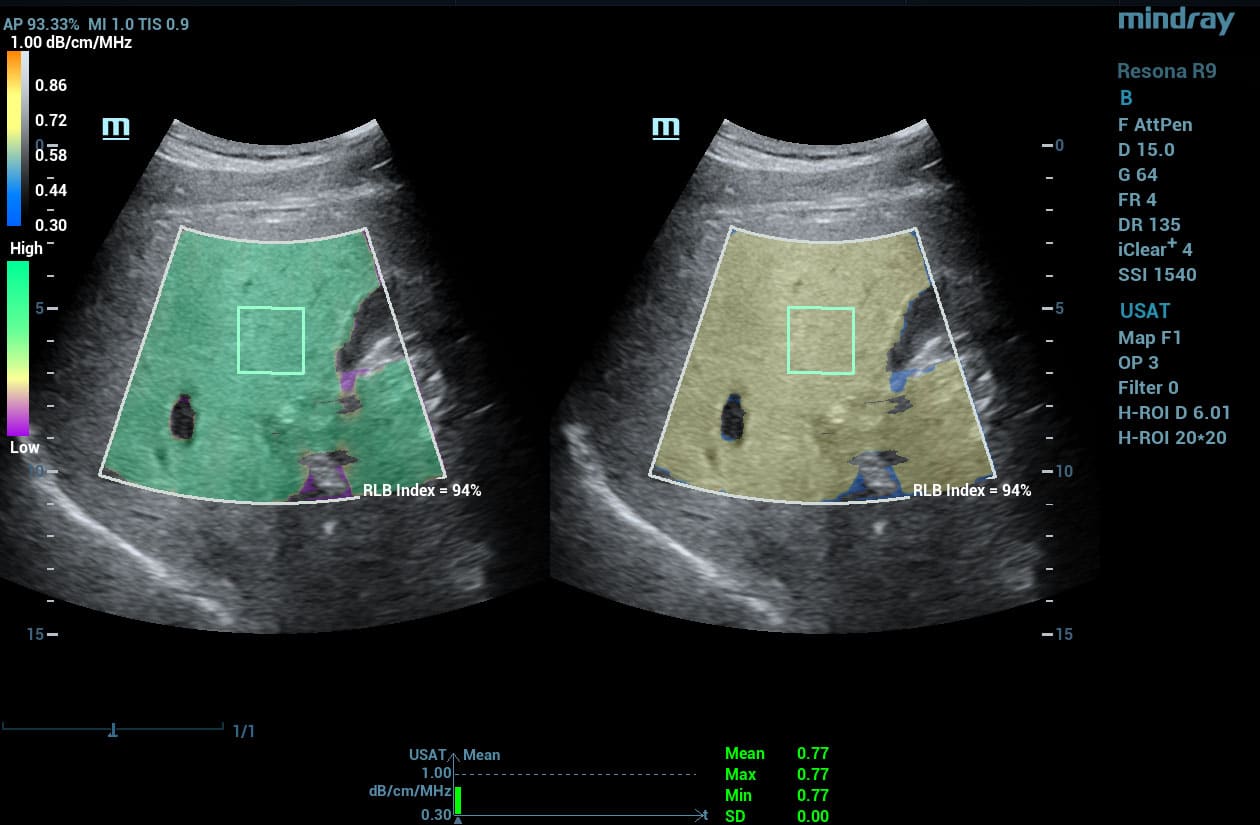

HD Scope

HD Scope is an advanced B-mode image processing technique that focuses additional imaging resources within a specified region of interest (ROI), analyzes the received channel data in unique ways, and applies various filtering and processing algorithms. This results in enhanced contrast resolution within the ROI based on the acoustic characteristics of varying tissue types.